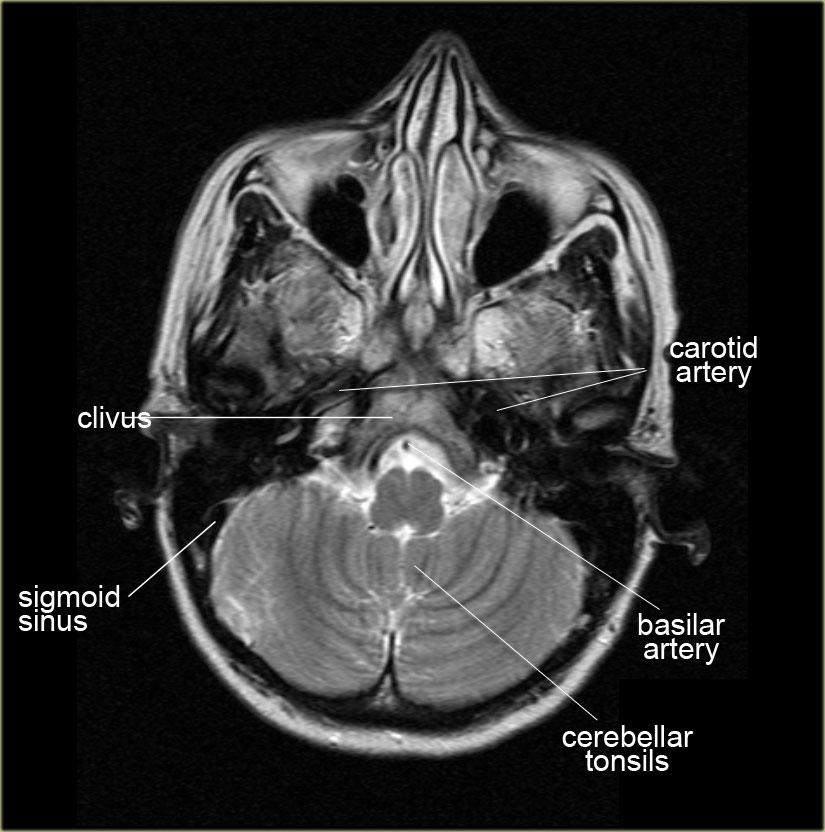

Giải phẫu trên mặt phẳng cắt ngang (Axial)

Các vùng giải phẫu đặc biệt